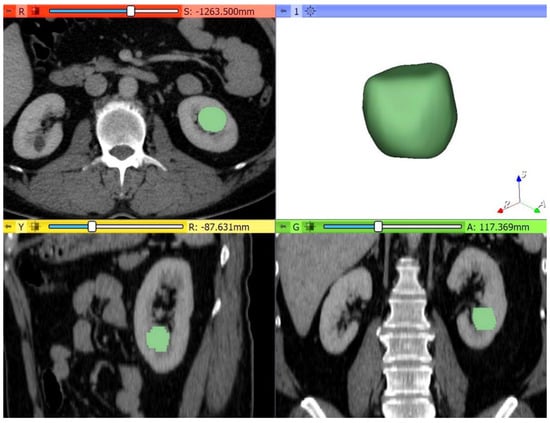

2.3. CT Image Analysis